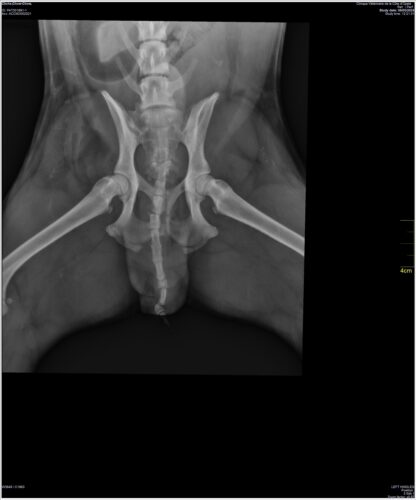

Mais une clinique qui dispose de scanner ou d’ IRM n’est pas une clinique classique, proposant aussi les opérations dites « de confort », et nous décidons de commencer par le plus évident : la castration couplée à la radiographie.

Waouh! Pour un chow dysplasique Unyx est un chow dysplasique! Il n’y a même plus de lettre pour qualifier le grade! Quel bon reproducteur il aurait fait ! Ah ! c’est vrai! Sommes-nous stupides ! « La dysplasie coxo-fémorale n’est pas héréditaire, c’est la faute des acquéreurs qui ne protègent pas assez les premiers mois des chiots… » Vous savez, autrefois on langeait-serré les bébés pour que les jambes soient droites en grandissant, faut faire pareil avec les chiots!…

A l’asso nous reprenons espoir: savoir Unyx dysplasique est presque un moindre mal tant on craignait un problème neurologique; certes l’un n’exclut pas l’autre mais nous avons une explication à ses pertes d’équilibre, on peut envisager une opération, (si oui laquelle et quand ?…) ou une rééducation par des méthodes douces, l’ostéopathie, la balnéothérapie qui ont aussi des résultats satisfaisants…